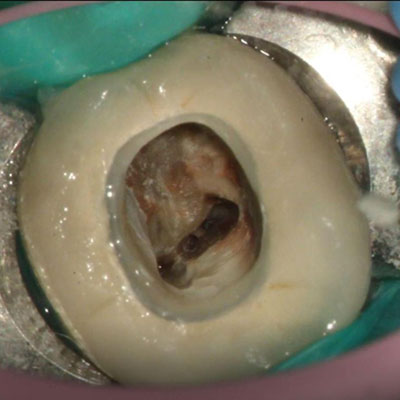

图为显微镜下一颗因蛀牙接受根管治疗的牙齿

很多人以为“蛀牙”只是小问题,直到疼到睡不着才重视——其实这可能是龋病发展成牙髓炎的信号。

龋病(蛀牙):简单说就是牙齿被“腐蚀”了。口腔里的细菌会分解食物残渣产生酸性物质,这些酸会慢慢破坏牙齿表面的牙釉质,形成黑洞(龋洞)。早期可能没感觉,一旦龋洞深入牙本质,吃冷热、甜食时就会酸痛,再不治就会“蛀”到牙髓!

牙髓炎:当龋病、外伤等让细菌侵入牙齿内部的“牙髓”(包含神经和血管),就会引发炎症。典型表现是剧烈疼痛——可能是夜间疼到醒、冷热刺激后疼得更久,甚至疼到分不清具体是哪颗牙,严重影响吃饭和睡眠。